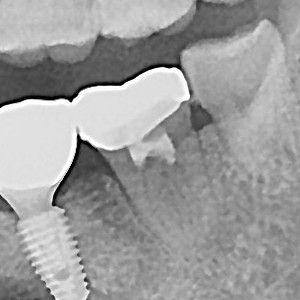

충치치료&신경치료 하루에 끝나는 신경치료

ab84f1a97a55df0651436bf31adcdd0f_1767396742_2926.jpg